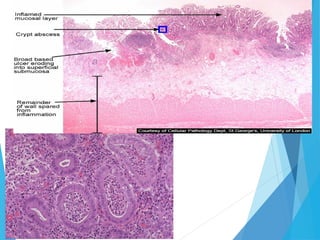

Pathological Feature

 Ulcerative colitis involves only the mucosa; it is

characterized by the formation of crypt abscesses and a

coexisting depletion of goblet cell mucin.

 In severe cases, the submucosa may be involved; in

some cases, the deeper muscular layers of the colonic

wall is also affected.

 Increased cellular infiltrate in the lamina propria,more

extensive and extends diffusely towards the deeper part

(transmucosal)

 Accumulation of plasma cells near the mucosal base, in-

between the crypt base and the muscularis mucosae (basal

plasmacytosis

 An irregular surface or a villiform surface and a disturbed

crypt architecture.

 Mucosal atrophy characterized by a combination of crypt

drop-out and shortening of crypts.

 Mucosal ulcerations and erosions, mucin depletion,

 Paneth-cell metaplasia and diffuse thickening of the

muscularis mucosae

H&E stain of a colonic biopsy showing a crypt

abscess:a classic finding in ulcerative colitis